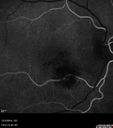

Macroaneurysm - No Leakage on FA - Fluid Absorbed - NO TREATMENT

87 year old female with decreased vision OD EXTENDED HPI: The vision in the right eye was good until a few days ago when she noticed that the vision was getting worse in the right eye. It could have been earlier and she might not have noticed it.

VA OD: sc20/100 NscJ16

VA OS: sc20/25-1 NscJ5-1

VA improved to 20/80 in 4 months and fluid absorbed without treatment

Macroaneurysm - Resolved without treatment417 views87 year old female with vision loss OD. Initial FA showed no leakage so no treatment was done and the fluid absorbed over 4 months. Initial VA 20/100, Final VA 20/80     (0 votes)